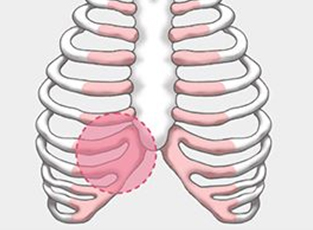

在精確的診斷基礎上, 指定精準的手術計劃